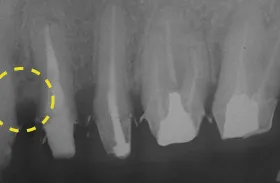

むし歯による前歯欠損の為来院されたケース

■治療前

■歯の根の引き上げ

■治療後

治療のポイント

歯の根の位置を引き上げ、抜歯。その日にインプラント治療へ。

自然の歯と変わらない審美性を取り戻し、非常に満足されています。

| 主訴 | 上顎の真ん中の歯が折れた |

|---|---|

| 治療方法 | 歯の根を引き上げることにより、増骨するので、その後1本のインプラントを埋入し治療した |

| 治療期間 | 約1年 |

| 通院回数等 | 10回 |

| 費用 | 550,000円(税込) |

| リスク・副作用 | 外科治療なしで増骨させた為、治療期間が長くなった |